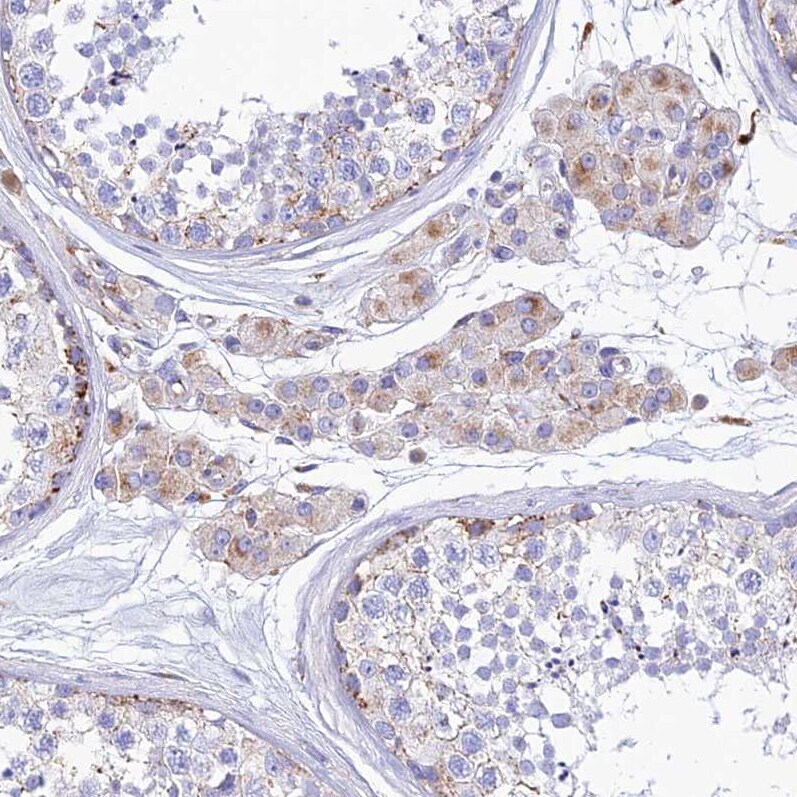

- Submitted by

- Invitrogen Antibodies (provider)

- Main image

- Experimental details

- Immunohistochemical analysis of SPNS1 in human pancreas using SPNS1 Polyclonal Antibody (Product # PA5-59813) shows very weak positivity in exocrine glandular cells as expected.